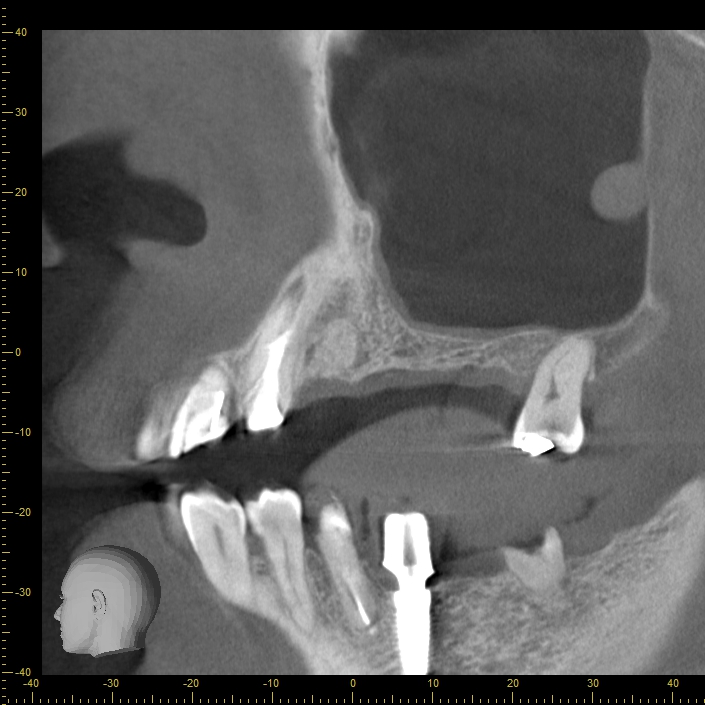

CT

インプラントは、骨の部分に埋め込む必要があります。骨には血管や神経が通っているため、埋め込む際はこれらを傷つけないように注意しなければなりません。

どこに血管や神経が通っているのかを把握するのに役立つのがCTです。CT検査を行うことで、お口の中を360度しっかり撮影できるので、安全な治療が行えるようになります

人為的ミスを最小限に抑えるために、当院ではSMOPガイドを導入しています。SMOPガイドとは、インプラントを入れる位置をコンピュータでシミュレーションできるシステムのことです。

CTで撮影したデータを取り込むことで、どのように治療を行っていくべきなのかをコンピュータが計算します。神経や血管を傷つけないサイズのインプラントを選んでくれるのはもちろん、インプラントをどの位置にどのような角度で入れるべきなのかまで緻密に判断してくれます。